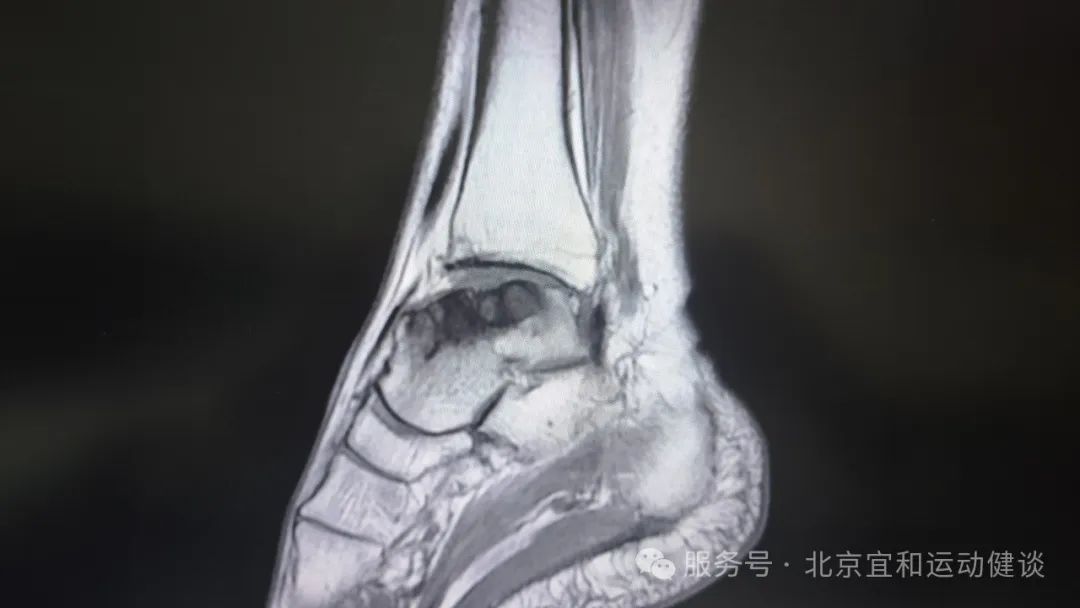

武主任和赵主任看了莉莉阿姨的影像学检查资料后,确诊莉莉阿姨是【踝骨关节病】,且距骨关节面已经明显损伤,最适合的手术方案是踝关节部分置换。

患者术前影像学检查资料